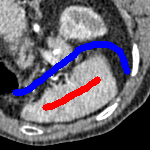

The motivation for this work comes from observing contradictions in using piecewise-constant intensity fitting terms in selective segmentation. Whilst good results are possible with this approach, the exceptional cases lead to severe limitations in practice. This is quite common in medical imaging as demonstrated in Fig. 1, where the target foreground has a low intensity. Given that the corresponding background includes large regions of low intensity, the optimal average intensities for this segmentation problem are and . For cases where , we see that by (1), almost everywhere in the domain . This means that it is very difficult to achieve an adequate result, without an over-reliance on the user input or parameter selection.

| (10) |

for and as defined in (33). This is consistent with respect to the intensities of the observed object and the concept of selective segmentation. In Fig. 3 we see the difference between CV and the proposed fitting terms for given user input on a CT image. For the CT image, the CV fitting terms are near 0 within the target region. This is despite there being a distinct homogeneous area with good contrast on the boundary. This illustrates the problem we are aiming to overcome. With the proposed fitting term this phenomenon should be avoided in cases like this. By defining as in (33) there is no contradiction if the foreground and background intensities of the target region are similar.